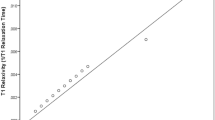

Supplementary Figure 1 Comparison of the apparent T1 and CoV depending on the method of analyzation. Y-axis are measurements made by the method described in the methods section. X-axis are measurements made in parametric maps. As evident from the figure, the measurements are well comparable between the two methods of analyzation.